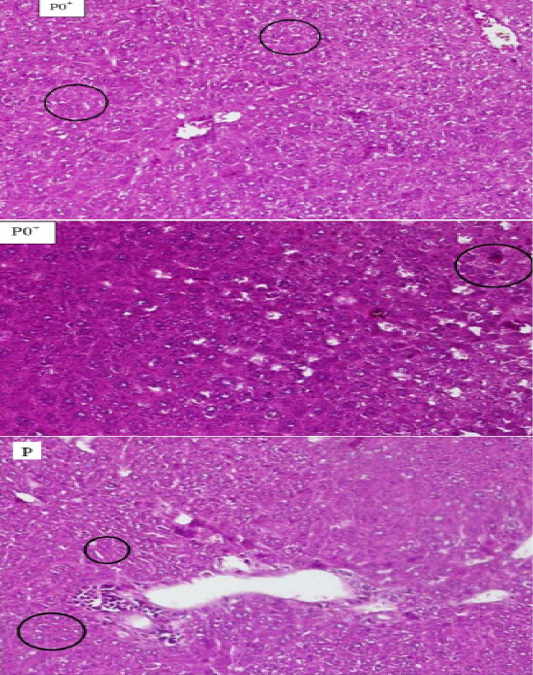

Figure 1

The comparison between hepatocyte Histopathology of mice (Mus Musculus) which experienced necrosis on the blood smears P0+, P0- and P. The circle shows the cell that experienced necrosis. The supply used Hematoxylin Eosin (HE) 200x magnification.